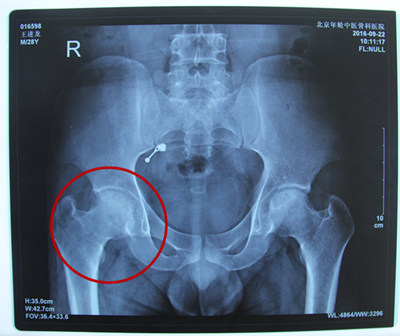

诊断结果:双侧股骨头缺血性坏死

病情描述:患者于2016年4月份因劳累后双髋关节疼痛且有跛行症状,以右侧为重,于当地医院诊断为“双侧股骨头坏死”,采用药物治疗,身体情况稍有好转,每次劳累后,疼痛加重,一经休息后情况稍有缓解,来院前一直也未正规治疗。2016年9月在残联的帮助下加入到了站立计划的项目中来。残联和站立计划的工作人员经实际考察发现患者在费用支付上存在一定的困难。经特殊批准得到了站立计划的全额救助。

2016年9月20日来到北京年轮中医骨科医院接受治疗。经年轮股骨头医师会诊后决定对其股骨头坏死病变区进行髋关节滑膜切除、清理并修正松解;采用年轮特色中医保守疗法,以特制中医中药调理病况,并由康复医师指导日常髋关节功能的恢复。